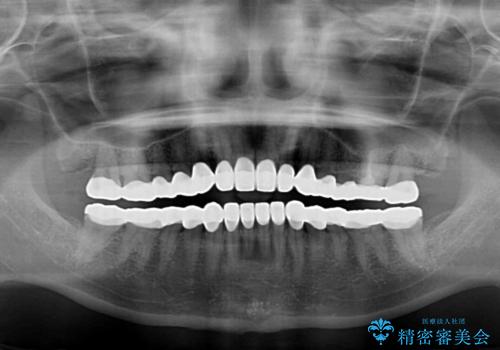

- 奥歯の銀歯をセラミックにしたいとのことで来院された患者様です。

当初は奥歯のみの治療をご希望でしたが、話を進めていくうちに、軽度ではあるものの、幼少期の薬の影響で歯が変色していることがコンプレックスであるということが分かりました。

長年歯の色が塞ぎ込んでいた部分があるとのことで、これを機会に全ての歯を真っ白にするために、オールセラミッククラウンにて補綴治療を行うこととしました。